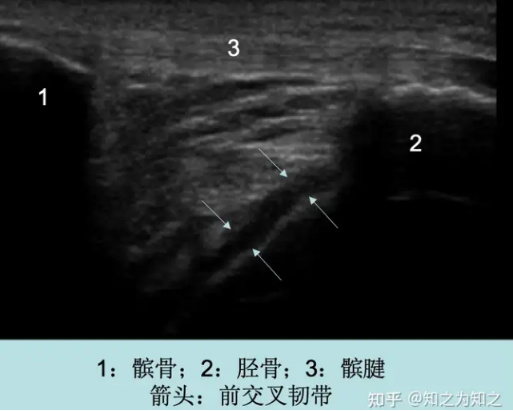

邓阿茂主任在查看患者报告后,立马联系超声科进行肌骨超声扫查,发现患者膝关节积液是损伤关节内积血,动态观察半月板、侧副韧带、支持带、脂肪垫均有损伤。

图片

确认病因后,邓阿茂主任决定使用肌骨超声引导下的精准治疗技术为主分期综合为患者进行对症治疗。在肌骨超声引导下精确将关节积血抽出,同时将生理盐水等治疗性药液注射在病灶处,从而最大限度地减少了关节内在的压力,提高了治疗的精准度和效果。经过大约20分钟的治疗后,患者右膝的胀痛与活动度改善。